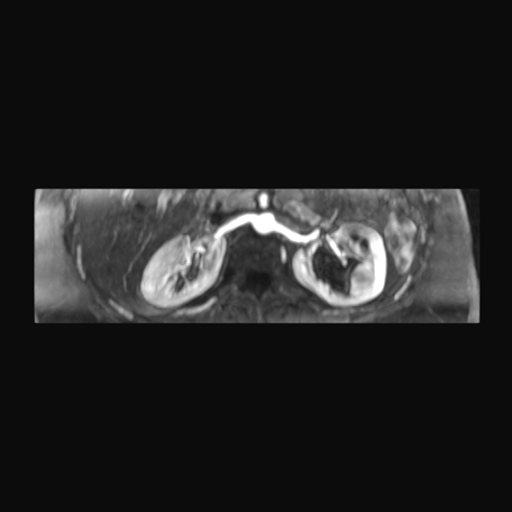

Los sistemas colectores del riñón derecho y del riñón izquierdo, muestran alteración de sus calices primarios y secundarios, mostrando dilatación, la pelvis renal y el uréter se observan de características normales lo que indica que no hay proceso obstructivo.

Se observa dilatación del sistema calicial sin proceso obstructivo compatible con una anormalidad del desarrollo de los sistemas colectores de ambos riñones, definiéndose como una “megacaliosis”

Desde el punto de vista anatómico e histopatológico, la mayoría de los autores coinciden en que la base de esta anomalía es un desarrollo anómalo de la médula renal: hay hipoplasia de las pirámides medulares, papilas renales malformadas o aplanadas, y acortamiento de los túbulos colectores, lo que se traduce en cálices más numerosos, ensanchados y de contornos facetados o “en trébol”.

A diferencia de la hidronefrosis, la corteza suele ser de espesor relativamente conservado y no existe un aumento sostenido de la presión intrapelviana.